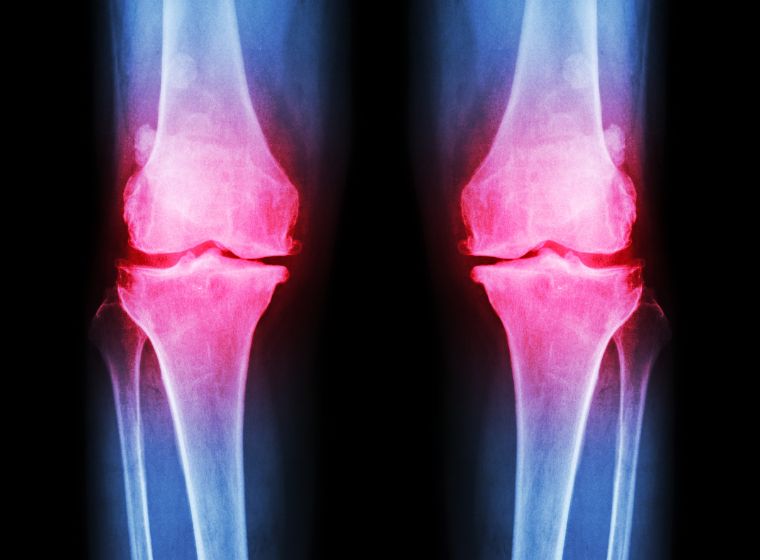

Остеоартрит (ОА) — одно из самых распространенных хронических заболеваний суставов, характеризуется постепенной деградацией хряща, что приводит к скованности, боли и снижению подвижности. Традиционные методы лечения, такие как медикаментозное лечение, физиотерапия и хирургия, часто направлены только на симптомы. Однако в настоящее время изучаются инновационные подходы, такие как терапия стволовыми клетками, для устранения основных причин остеоартрита, особенно для тех, кто задается вопросом, могут ли стволовые клетки помочь при остеоартрите?